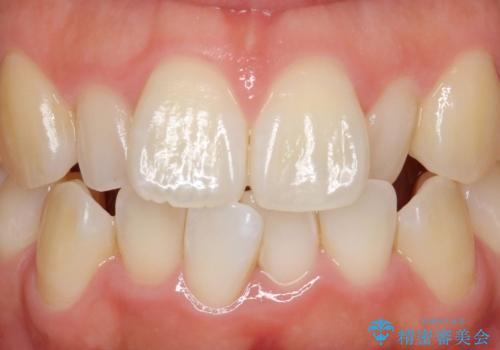

矮小歯 セラミッククラウンで綺麗に 30代女性

全顎的に歯並びにがたつきがあり、上の側切歯(上顎両側2)は生まれつき小さい歯(矮小歯)でした。

矯正治療後、矮小歯をセラミッククラウンにより理想的な歯の大きさに仕上げました。